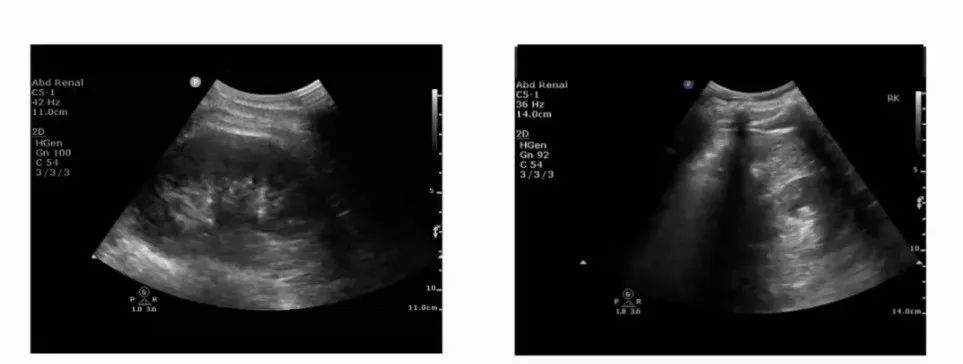

2.3个周径

通过评估肾脏周径,可以有效监测肾脏功能。正常情况下,肾脏长10~12 cm,宽5~6 cm,厚3~4 cm。

肾脏正常大小超声图

3.3个内测量

评估内测量与评估周径作用相似,包括肾实质厚度(1~2 cm,通常1.5 cm)、肾皮质厚度(8~10 mm)、管状液暗区内径(<1 cm)、肾窦大小(约占肾脏的1/2~2/3)。